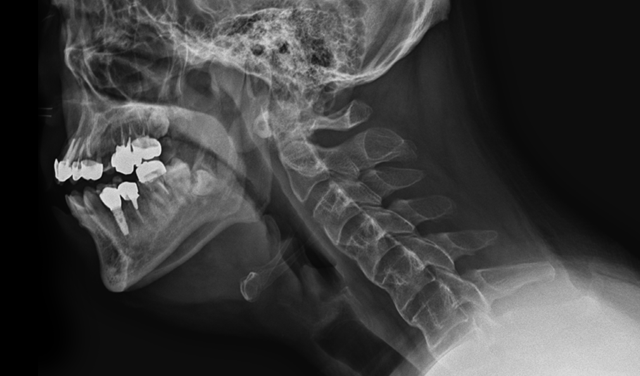

- 두경부암 치료 후 목이 뻣뻣하고 음식을 삼키기 어려움 → 목 근육과 신경의 섬유화